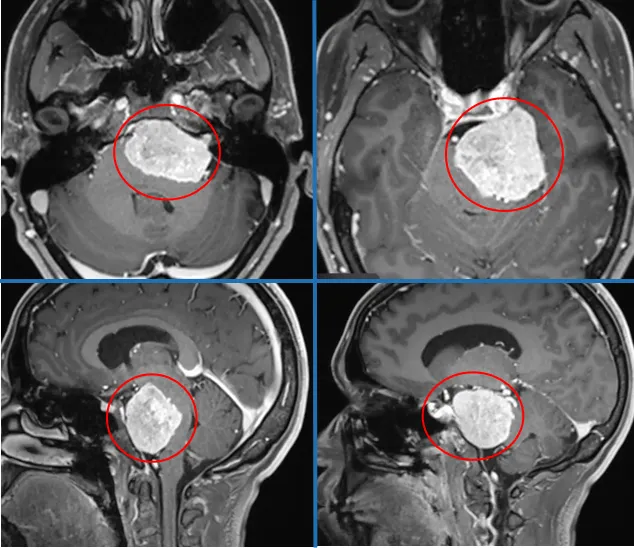

下面这个脑瘤是不是很大,位置很不好?岩斜区脑膜瘤,已经挤压脑干。我们知道岩斜区脑膜瘤沿着上2/3斜坡生长,位于颈静脉孔上方,岩斜区颅神经孔内侧。瘤体被包括脑干、基底动脉、III-VIII对颅神经、海绵窦及蝶鞍在内的众多神经血管结构紧密包围,该部位难以接近,手术入路设计尤为困难。

随着岩斜区脑膜瘤的不断生长,可将脑干向后方及对侧推挤,与基底动脉远端、分支和穿支血管关系密切,瘤体侧方常被颅神经所遮盖,肿瘤累及海绵窦常见。由于瘤体毗邻的颞骨解剖复杂,导致该部位肿瘤为多个易损结构包绕,术中显露困难。

术前MRI

这台手术,INC福教授采用经典的颞-顶-枕L形开颅联合细致的岩骨切除术。手术伊始,通过识别关键骨性标志、进行整形性乳突切除术并充分显露乙状窦与窦硬膜角,以构建坚实的手术基础。